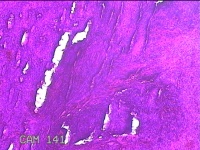

宫颈6点、12点组织

性别

女

年龄

57岁

临床诊断

子宫颈上皮内瘤变[CINⅢ级];子宫颈肿瘤

一般病史

阴道不规则出血1年。

标本名称

大体所见

1.“宫颈6点组织”:灰白粉红色组织1.3x0.8x0.3cm一块。 2.“宫颈12点组织”:灰白粉红色组织1.5x0.7x0.2cm一块。

图4